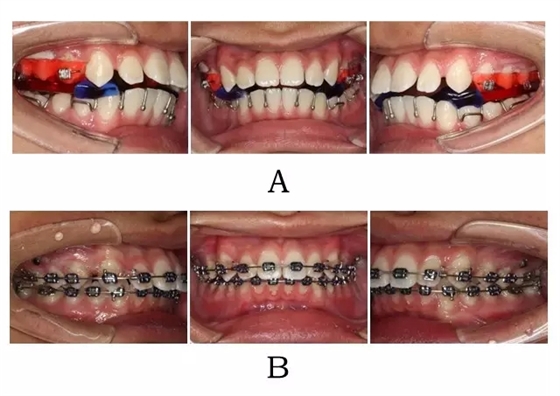

圖 4-5:混合 I I 型突面畸形 SGTB 矯形及后期常規(guī)固定矯治。

(A)SGTB 矯形 (B)后期固定矯治

Figure 4-5. SGTB therapy for merged prognathism (Type II). (A) SGTB orthopedics at early stage.(B) Fixed orthodontics at late stage.

(2) 骨性嚴(yán)重、上頜牙內(nèi)傾性代償嚴(yán)重且已生長發(fā)育完全停止的成人,可考慮用正頜正畸聯(lián)合治療。術(shù)前治療的要點(diǎn)是上前牙有限度的直立性去代償及下頜 Spee曲線的整平。由于下頜自動前移釋放的潛力有限,在上前牙去代償后往往創(chuàng)造足夠的覆蓋,通常不需要通過拔中段牙創(chuàng)造覆蓋。術(shù)式通常是雙頜(上頜 LeFort I +下頜 BSSRO),由于頦部形態(tài)較好,一般不需要附加頦成形術(shù)[10](圖 4-7;4-8;4-9)。